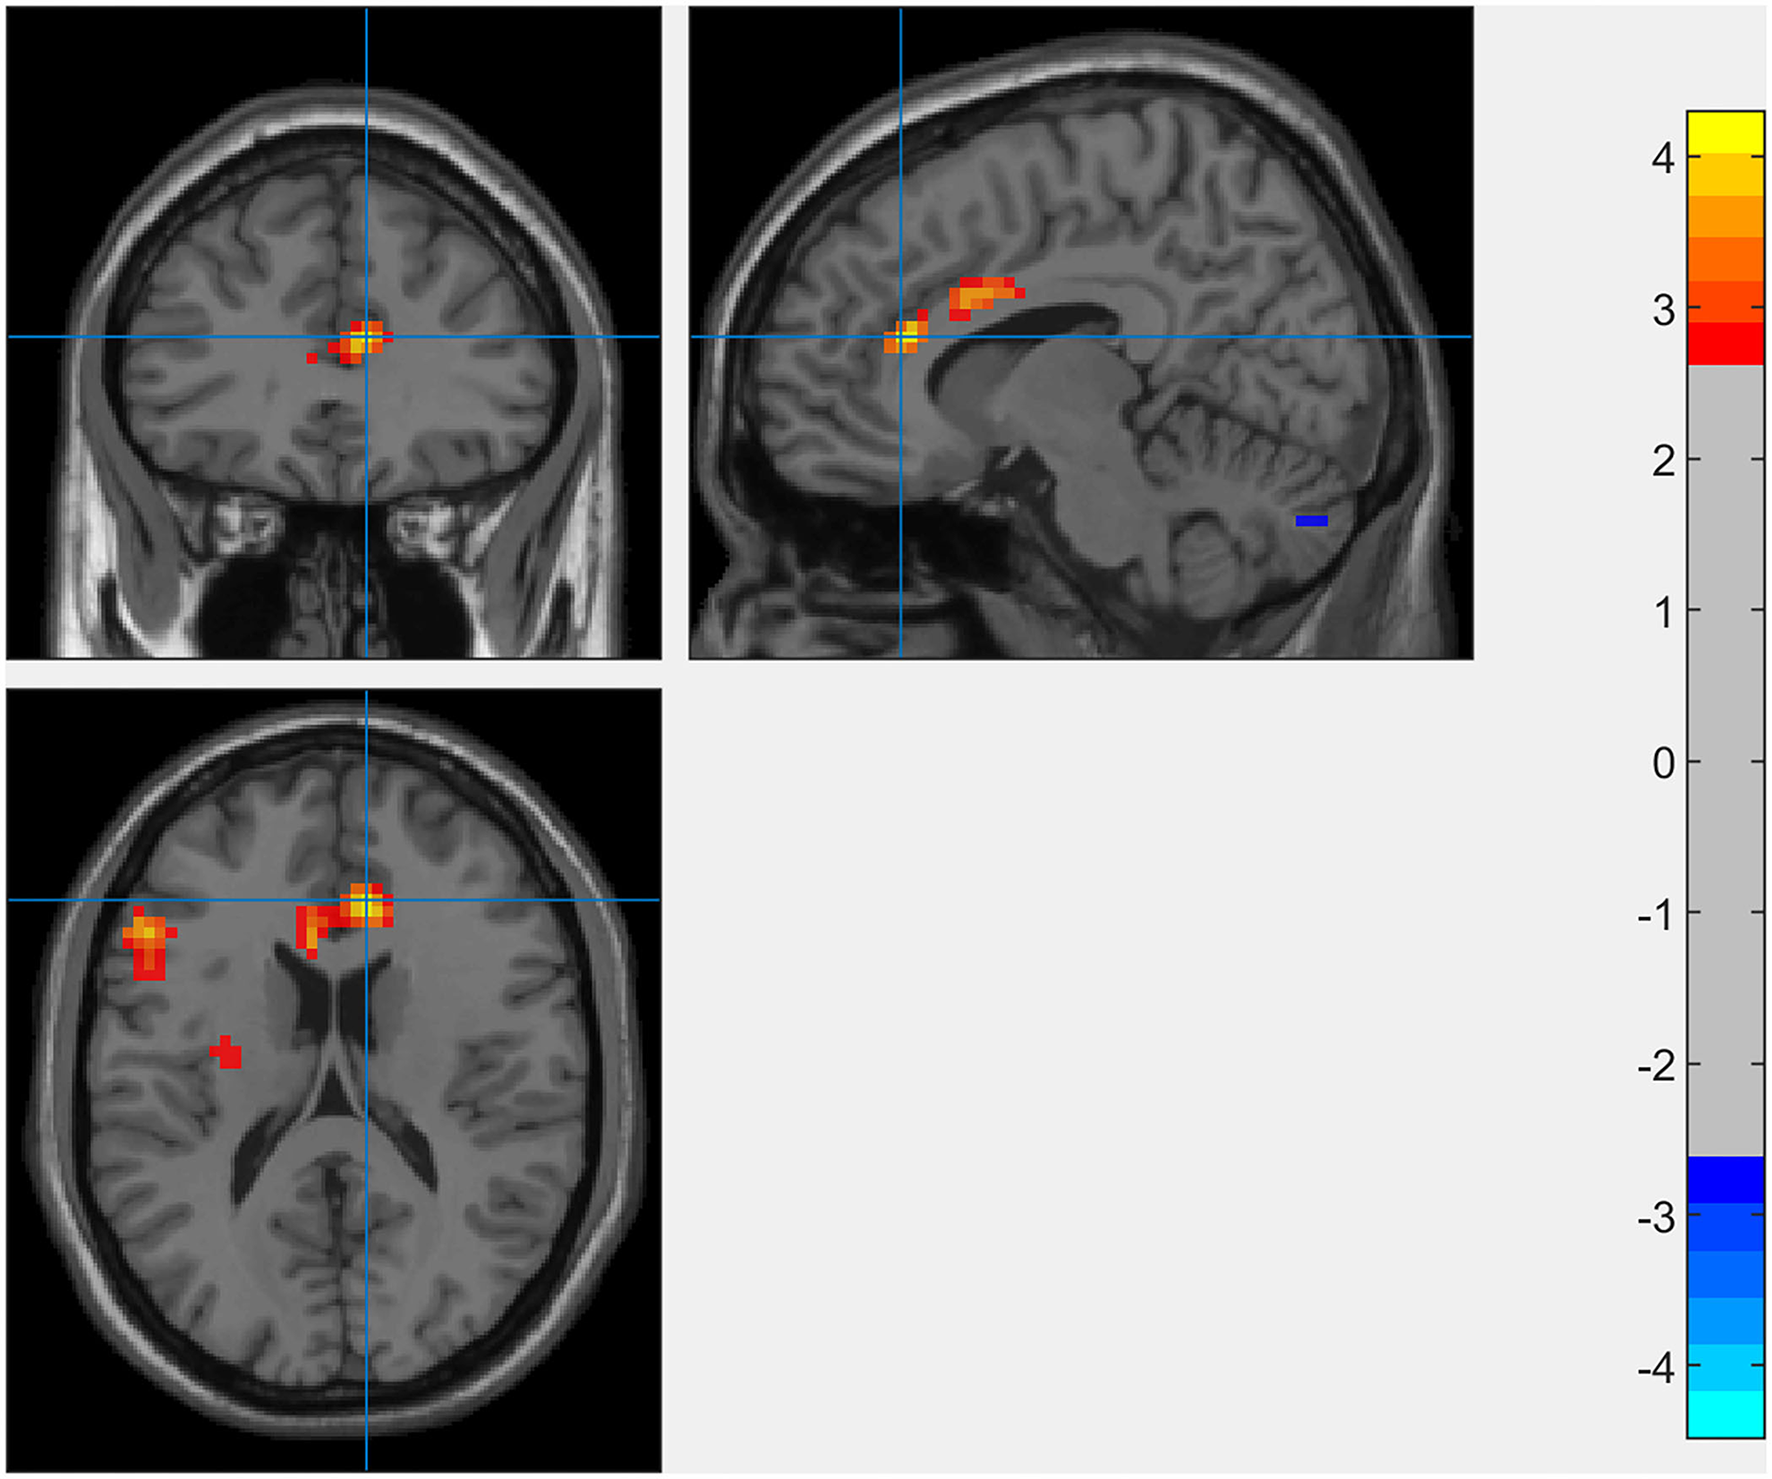

Results of whole-brain analysis

The results of the whole-brain analysis showed that the interaction effect between SCCS and RSES was significant in the right dACC (9, 33, 18) with [−1 1] t-contrast (see Figure 3 and Table 1).

Figure 3

Whole-brain analysis of the interaction between SCCS and SES when predicting spontaneous activation of the brain (GRF-corrected p < 0.005 at the voxel level with p < 0.05 at the cluster level).